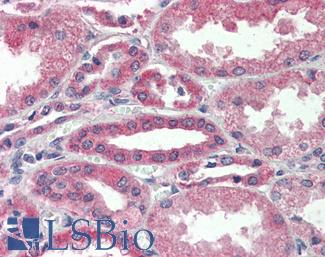

Cyclooxygenase 2 (COX-2 / PTGS2)

Anti-COX-2 antibody IHC of human kidney. Immunohistochemistry of formalin-fixed, paraffin-embedded tissue after heat-induced antigen retrieval. Antibody LS-B1608 concentration 5 ug/ml.